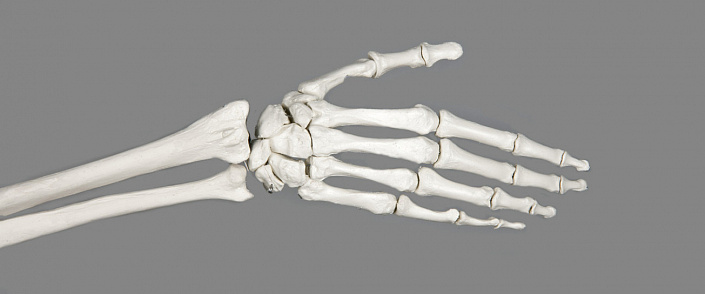

Анатомия кисти руки человека довольно сложна. Поскольку это очень подвижная часть тела, в ней множество костей и суставов, связок и мышц, также человеческие пальцы, в отличие от конечностей животных, имеют ногти. Кожа рук также отличается от кожного покрова тела, имея специфические складки и особую чувствительность. Итак, начнём с обзора костей. Кости кисти делятся на три отдела: запястье, включающее восемь костей; пясть, состоящая из пяти длинных костей, и пальцы, насчитывающие в общей сумме четырнадцать фаланг. Фаланги относятся к трубчатым костям, в отличие от остальных костей, составляющих кисть. Все кости довольно мелкие и расположены друг к другу очень близко.

Благодаря тому, что костей много и они небольшие, кисть имеет такую пластичность и подвижность, однако из-за этого при травмах работоспособность кисти заметно снижается. Кости запястья образуют как малоподвижные соединения (например, в области запястья), так и суставы. Лучезапястное соединение имеет форму полукруга и обеспечивает сгибание и разгибание кисти. Это очень сложный сустав, дающий кисти широкий диапазон движений. Кости запястья соединены между собой связками и образуют прочное сочленение, способное выдерживать большие нагрузки при опоре на кисть. У основания большого пальца расположен седловидный сустав, позволяющий совершать движения в двух осях, что делает большой палец очень функциональным.

Кости фаланг имеют шаровидные соединения, что позволяет пальцам сгибаться только в одной плоскости. Из-за этого пальцы весьма подвержены травмам. В отличие от остальных пальцев, насчитывающих по три фаланги, большой палец короче и состоит всего из двух костей. Кисть имеет широкую сеть инервации, отвечающую за осязание, движение, работу сальных и потовых желёз и терморегуляцию. Вообще руки тесно связаны с психическим состоянием человека. В моменты стресса руки часто трясутся, немеют, из них всё валится, человек утрачивает способность владеть ими в полной мере. Также при эмоциональных всплесках ладони могут похолодеть или вспотеть.